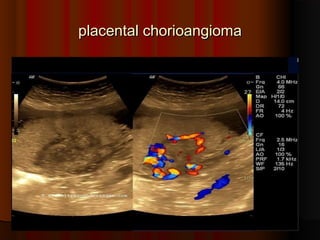

placental chorioangioma

 Sonography of the placenta in

Sonography of the placenta in

this 16 week pregnancy shows

a large, solid mass, that is non

calcific and shows mild

vascularity (vascular) and

excludes placental hematoma

excludes placental hematoma.

.

and shows many cystic spaces

within it

within it.

. This tumor of the

This tumor of the

placenta lies close to the cord

insertion site

insertion site.

. Ultrasound

Ultrasound

images of this type of placental

mass are highly suggestive of

placental chorioangioma.